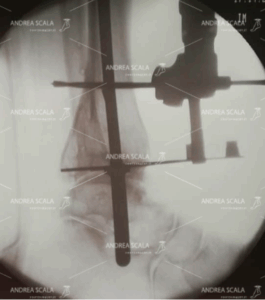

La RXgrafia intra-operatoria mostra la visione laterale del sistema di allineamento della protesi di caviglia, applicato all’esterno all’osso della gamba del paziente. Applicato all’asta di guida si vede una lunga barra sovrapposta alla tibia. Si vede anche una sottile linea metallica perpendicolare all’asta longitudinale, che aiuta ad impiantare la protesi perpendicolare all’asse longitudinale della gamba.

N.B. I due fili metallici che si vedono nella radiografia sono esiti di precedenti interventi.